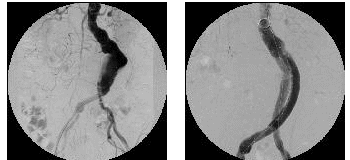

大動脈瘤ステントグラフト(EVAR)

胸部・腹部の大動脈に出来た巨大な瘤に人工血管を挿入して破裂を防ぎます。

手術に比べて、低侵襲的です。(傷跡は股関節部分の約5cm程度)